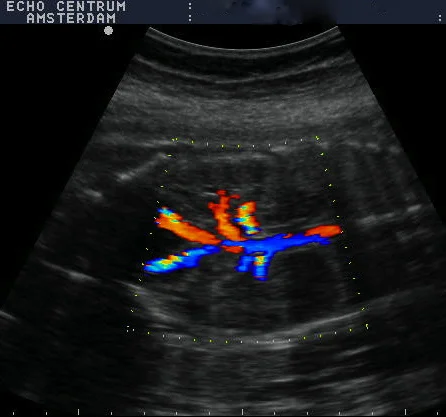

Onlangs had ik een hele leuke ervaring. Ik ben een gepensioneerd gynaecoloog, en was vroeger zeer begaan met mijn verloskundige patiënten. Mijn schoondochter en zoon nodigden mij uit om mee te gaan naar een "pretecho"van dr. Papa in Amsterdam. Wij, gynaecologen, hebben geweldige vooroordelen tegen een zogenaamde pret echo en vinden ze vaak overbodig. Nou dit pakte anders uit. We werden verwelkomd door een bijzonder charmante, leuke en vlot bespraakte Nederlandse Antiliaan: Elvin Papa, arts echoscopist. Daar zat hij in zijn spreekkamer, in een prachtig pand, achter een prachtig echo apparaat, dat voor mijn toenmalige ziekenhuis te duur was om voor ons gynaecologen aan te schaffen!! Alles werd getoond, het hele lichaampje van de baby. Alle organen, het geslacht, hart en bloedvaten noem maar op. Prettig was dat je in 3D een hele goede indruk krijgt van het gezichtje. Het hele onderzoek verliep voorspoedig en was heel relaxed. Papa doet veel aan nascholing en houdt de ontwikkelingen op echo gebied heel goed bij. Echo onderzoek kan heel vervelende zaken aan het licht brengen. Wij hadden een goed nieuws echo, dus dat is feest en lol. Belangrijk lijkt mij wel dat je met een slechte echo bij Elvin Papa in goede handen bent. Hij zal weten hoe je te troosten en hoe je door te verwijzen. Hopelijk hoeft dat niet vaak. Ik wens hem nog veel succes toe.

Bij deze willen wij je nog even bedanken voor de mooie en bijzondere echo die je van onze tweeling hebt gemaakt (de echo lukte zo goed!). Aangezien we ons nogal veel zorgen maakten was de echo precies de positieve input die we nodig hadden. We zijn natuurlijk een beetje beroepsgedeformeerd en wij vonden het schitterend dat je met de moderne technieken (je superecho-apparaat!!) de anatomie van die piepkleine mensjes zo goed kunt zien! Nogmaals ontzettend bedankt.